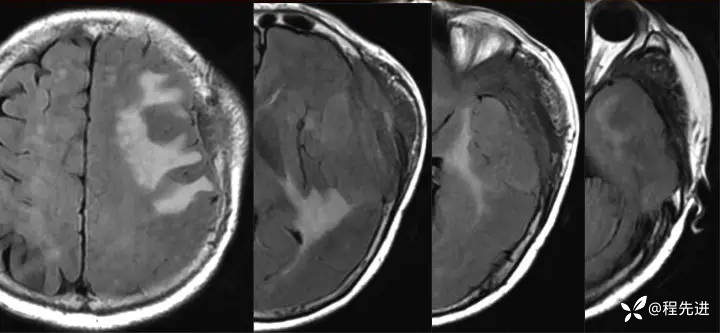

1月余后:

img